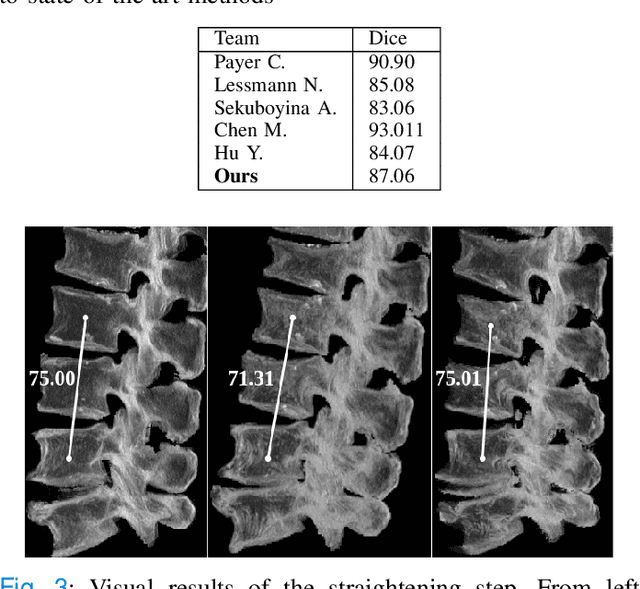

Abstract:Symptomatic spinal vertebral compression fractures (VCFs) often require osteoplasty treatment. A cement-like material is injected into the bone to stabilize the fracture, restore the vertebral body height and alleviate pain. Leakage is a common complication and may occur due to too much cement being injected. In this work, we propose an automated patient-specific framework that can allow physicians to calculate an upper bound of cement for the injection and estimate the optimal outcome of osteoplasty. The framework uses the patient CT scan and the fractured vertebra label to build a virtual healthy spine using a high-level approach. Firstly, the fractured spine is segmented with a three-step Convolution Neural Network (CNN) architecture. Next, a per-vertebra rigid registration to a healthy spine atlas restores its curvature. Finally, a GAN-based inpainting approach replaces the fractured vertebra with an estimation of its original shape. Based on this outcome, we then estimate the maximum amount of bone cement for injection. We evaluate our framework by comparing the virtual vertebrae volumes of ten patients to their healthy equivalent and report an average error of 3.88$\pm$7.63\%. The presented pipeline offers a first approach to a personalized automatic high-level framework for planning osteoplasty procedures.